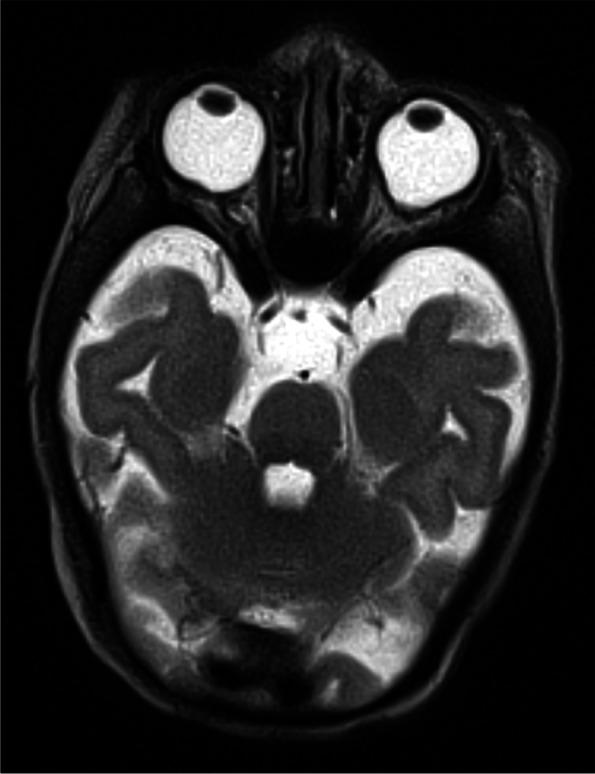

CHARGE syndrome is a relatively common cause of deafness and blindness resulting from failure to form the primordia of specific organs due to deficient contribution of neural crest cell derivatives. The majority of CHARGE syndrome cases are caused by heterozygous mutations in CHD7 on chromosome 8q21. Those with CHARGE syndrome without CHD7 mutation typically do not have an identified genetic defect. 7q11.23 duplication syndrome is associated with mild facial dysmorphism, heart defects, language delay, and autism spectrum disorder. In the current literature, 7q11.23 duplication has not been associated with CHARGE syndrome, retinochoroidal colobomas, or significant ear abnormalities.

We describe a patient with 7q11.23 duplication syndrome and clinical CHARGE syndrome with no variant in CHARGE-associated genes.